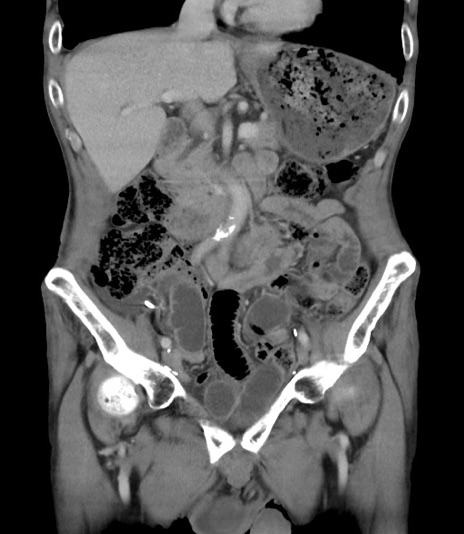

横断像

【症例】 70歳代男性

【主訴】右鼠径部腫瘤、疼痛

【現病歴】本日朝より上記主訴あり、受診。

【既往歴】膀胱癌にて膀胱全摘、両側尿管皮膚瘻

【データ】WBC 5600、CRP 0.56